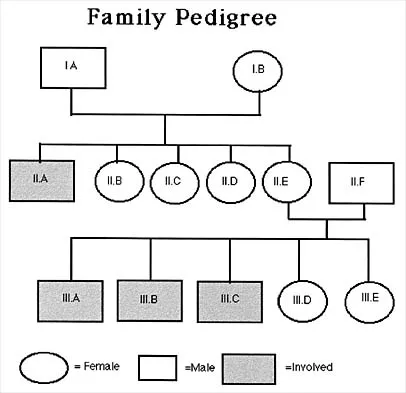

Figure 53 shows the pedigree of a family with an unusual type of muscular dystrophy. This pedigree is most consistent with what type of inheritance pattern?